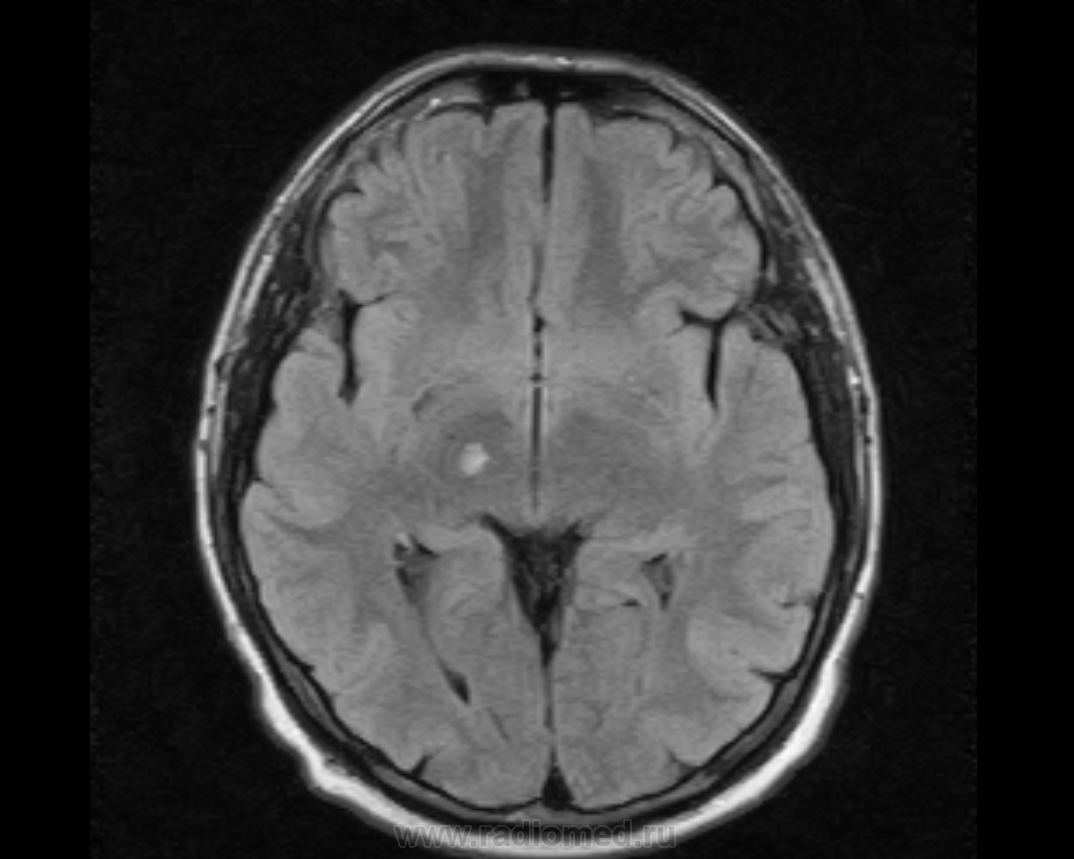

М, 27 лет. Жалобы на головные боли. ЧМТ в анамнезе. Стационар выставил внутримозговую гематому по КТ, полечили, отпустили.  К нам пришел на контроль.

Локализация таламус, граница коркового/мозгового, похоже на множественные кавернозные ангиомы. То, что в левой лобной?

Хочу посоветоваться с коллегами).  Дифференциальный ряд построить. Например токсоплазмоз, метастазы....в общем жду.

Сложно представить у молодого человека и каверномы, и метастазы одновременно.

Наверное, все же множественные каверномы, слева -осложненная кровоизлиянием.

Пришел к выводу, что сдесь все таки не каврномы, а мелкоочаговые кровоизлияния (ДАП). Учитывая травму и пребывание после этого  пациента в коме.